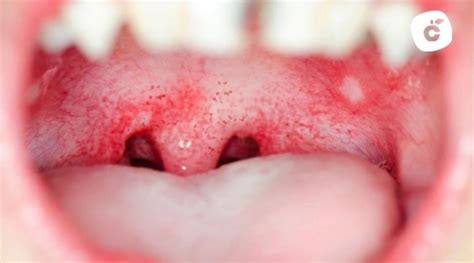

Manchas Rojas en el Paladar

Muchos pacientes acuden a la consulta tras manifestar molestias o notar la aparición de manchas rojas en el paladar. Las manchas rojas en el paladar no aparecen por una sola causa específica. De hecho, son diferentes las variantes que pueden determinar su aparición, porque la sintomatología de estas se diferencian por el tipo de patología. Son diferentes los tipos de manchas en el paladar y se distinguen según los síntomas y patologías.

- Las amígdalas se vuelven rojas, inflamadas y, en ocasiones, presentan manchas blancas o rastros de pus.

- Pequeños puntos rojos pueden aparecer en la parte posterior del paladar